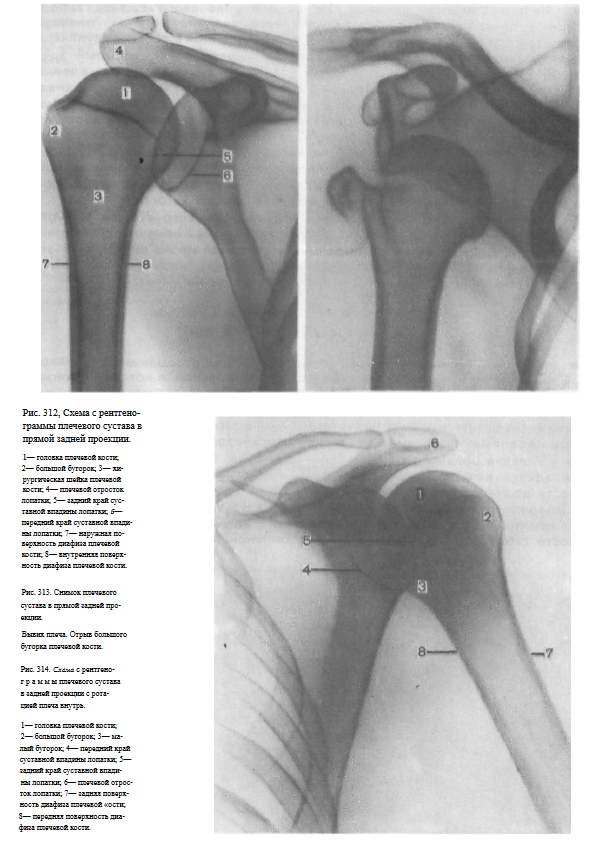

На снимках плечевого сустава хорошо видны головка плечевой кости, суставная впадина лопатки, плечевой отросток лопатки.

На рентгенограмме, произведенной в условиях супинации кисти, хорошо виден большой бугорок плечевой кости, который здесь является краеобразующим (рис.312, 313). На снимках, произведенных в условиях пронации кисти, большой бугорок виден хуже, но по медиальному контуру над хирургической шейкой становится виден малый бугорок (рис.314). Медиальный и латеральный контуры тела плечевой кости при этих двух вариантах укладки на снимках образованы разными ее поверхностями. На снимке при супинации кисти медиальный контур образован внутренней, а латеральный — наружной поверхностью тела плечевой кости; на снимке при пронации кисти медиальный контур отображает переднюю, а латеральный — заднюю поверхность тела плечевой кости.

Наиболее информативными для оценки плечевого сустава являются снимки, выполненные в условиях разгибания верхней конечности и супинации кисти. Снимки в задней проекции с ротацией плеча внутрь являются дополнительными или же выполняются в тех случаях, когда снимок в прямой задней проекции с разгибанием руки произвести не удается.